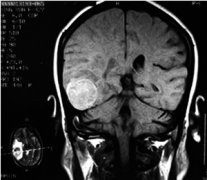

蛛網(wǎng)膜囊腫,屬于先天性良性腦囊腫病變,是由于發(fā)育期蛛網(wǎng)膜分裂異常所致。囊壁多為蛛網(wǎng)膜、神經(jīng)膠質(zhì)及軟腦膜,囊內(nèi)有腦脊液樣囊液。囊腫位于腦表面、腦裂及腦池部,不累及腦實(shí)質(zhì)。多為單發(fā),少數(shù)多發(fā)。本病多無(wú)癥狀,體積大者可同時(shí)壓迫腦組織及顱骨,可產(chǎn)生神經(jīng)癥狀及顱骨發(fā)育改變。本癥多見(jiàn)于兒童及青少年,男性較多,左側(cè)較右側(cè)多見(jiàn)。蛛網(wǎng)膜囊腫按病因不同可分為先天性和繼發(fā)性(外傷性及感染后)兩大類(lèi),按部位不同可分為顱內(nèi)型及脊髓型兩類(lèi)。

蛛網(wǎng)膜囊腫,屬于先天性良性腦囊腫病變,是由于發(fā)育期蛛網(wǎng)膜分裂異常所致。囊壁多為蛛網(wǎng)膜、神經(jīng)膠質(zhì)及軟腦膜,囊內(nèi)有腦脊液樣囊...【詳細(xì)】